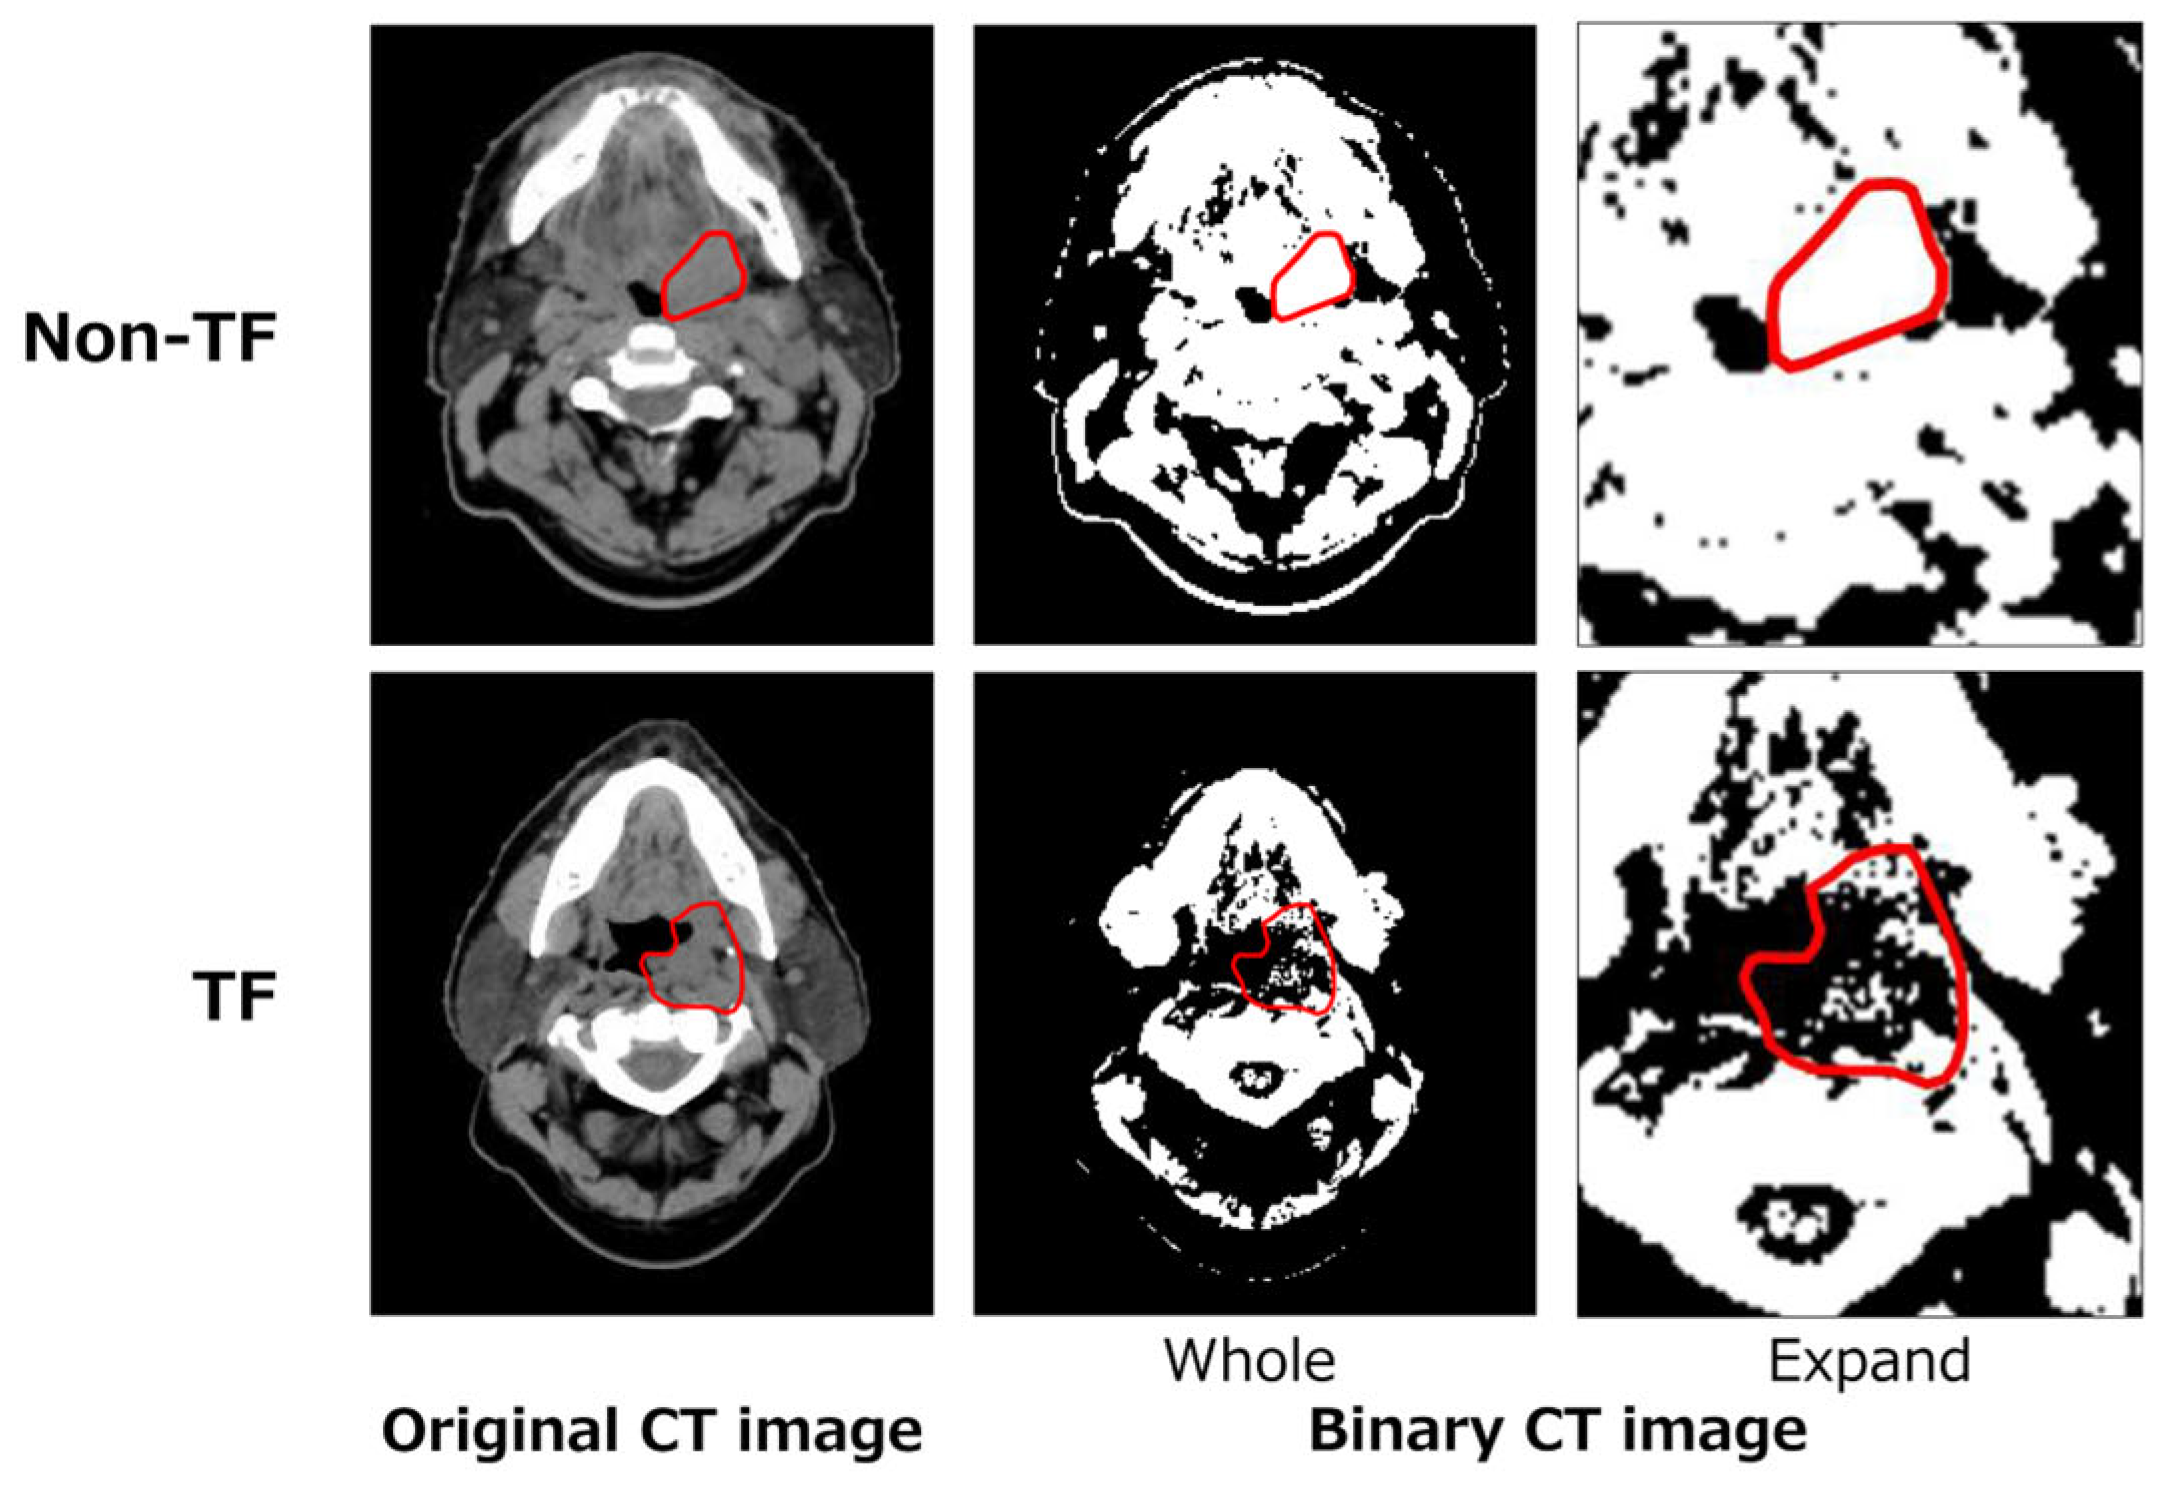

2.3.2. Local Binary Pattern (L) Feature

2.3.3. Topological (T) Feature

2.3.4. Deep (D) Feature